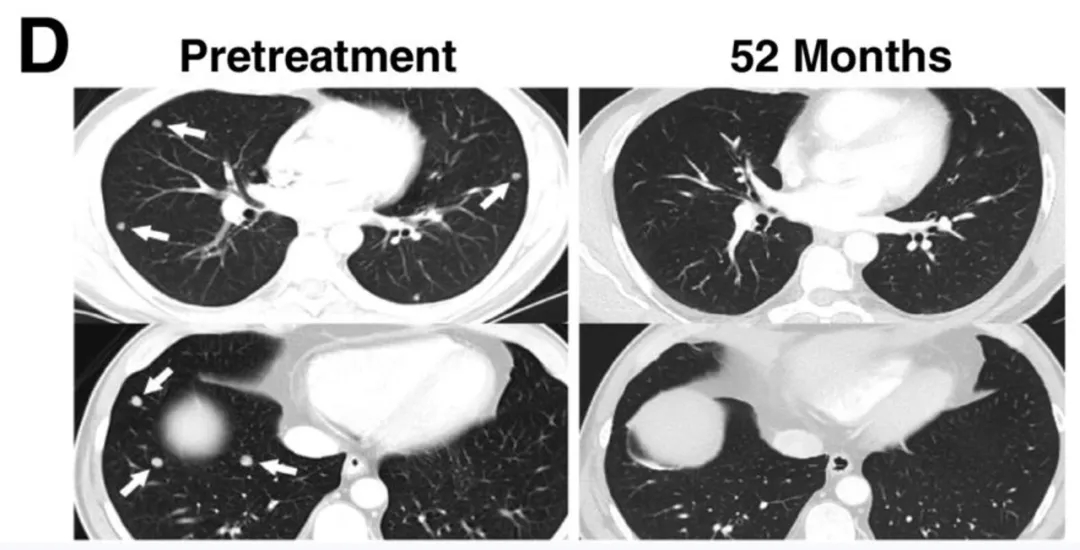

在黑色素瘤患者中,11例缓解患者均在首次接受1G4-αLYTCR转导T细胞治疗后,出现客观缓解。其中4例患者达到完全缓解(CR),3例在治疗后40~58个月仍维持完全缓解。另有7例患者达到部分缓解(PR),持续时间为3~28个月;37号患者在输注后6个月仍维持部分缓解,因出现无关第二种癌症终止随访。该组患者3年和5年总生存率估计值均为33%(详见下图B)。

值得关注的是,CT及放射学检查清晰记录了典型患者的肿瘤消退情况:29号患者的肝脏和肺部多发转移灶完全消退(详见下图C/D),疗效维持54个月以上。